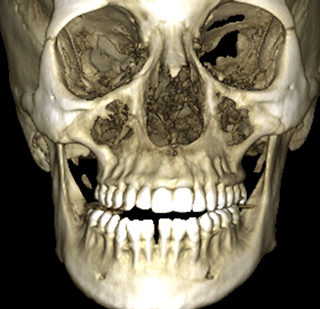

CBCT Scan

Cone beam computed tomography (CBCT) offers 3-D visualization and more accurate imaging compared to conventional radiographs. Radiodent 3D offers precise and focused, small and large view CBCT(Cone beam computed tomography) scans with a very affordable pricing structure depending upon the field of interest.